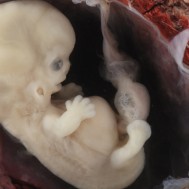

Baby: Week 6

You’re now making spontaneous movements, and can twitch your trunk and limb buds

Each day, changes make you more recognisable as a small person just like you. Now your lungs are forming![1] Brain function, as measured by EEG waves, can be recorded within days.[2] Nerve cells in the brain are connecting, forming primitive neural pathways. Your hands can bend at the wrist, and webbing is disappearing from your feet. Your tail is just about gone. Tastebuds are forming on your tongue.[3] You’re now making spontaneous movements, and can twitch your trunk and limb buds.[4]